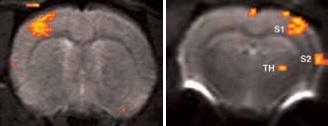

Figure 2. BOLD activation at 11.7 Tesla using the quadrature surface coil with a resolution of (left) 300 x 300 x 2000 μm3 for high quality and (right) 150 x 200 x 2000 μm3 for high sensitivity. Image Credit: Bruker BioSpin Group

Using older DBX electronics and linear surface coils at 7.0 Tesla, BOLD contrast with 400 x 400 x 2000 μm3 resolution can be obtained. Combined with T2-maps, loss of functional activity and its instant recovery as well as stroke lesion (Figure 1) was defined[4,5]. A combination of faster AVANCE II readout electronics, quadrature surface coil, and higher field strength of 11.7 Tesla increased both resolution and SNR to less than 200 x 200 x 2000 μm3, which is more than sufficient to identify the tiny structures along the neuronal activity pathway like the thalamus and secondary somatosensory cortex S2 (Figure 2) with BOLD contrast.